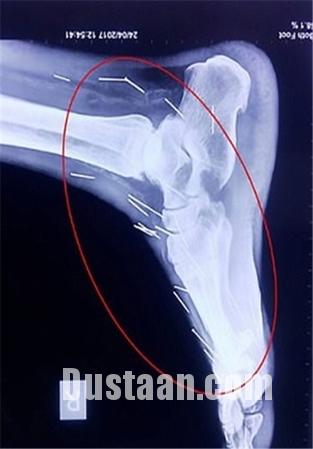

پزشکان با مراجعه مردی جوان به بیمارستان که عنوان داشت در ناحیه گلو و کف پایش احساس درد دارد، اقدام به عکسبرداری از وی کردند، انها در کمال تعجب مشاهده کردند که بیش از ۷۵ سوزن در گلو و دیگر بخش های بدن او فرو رفته است!

«بادریلال مینا» که از اهالی ایالت راجستان است، از وجود این سوزن ها اظهار بی اطلاعی می کند! اما حقیقت چیز دیگریست چرا که فرو رفتن این سوزن ها در بدن وی قطعا بدون درد نبوده و وی از وجود سوزن ها مطلع بوده است.